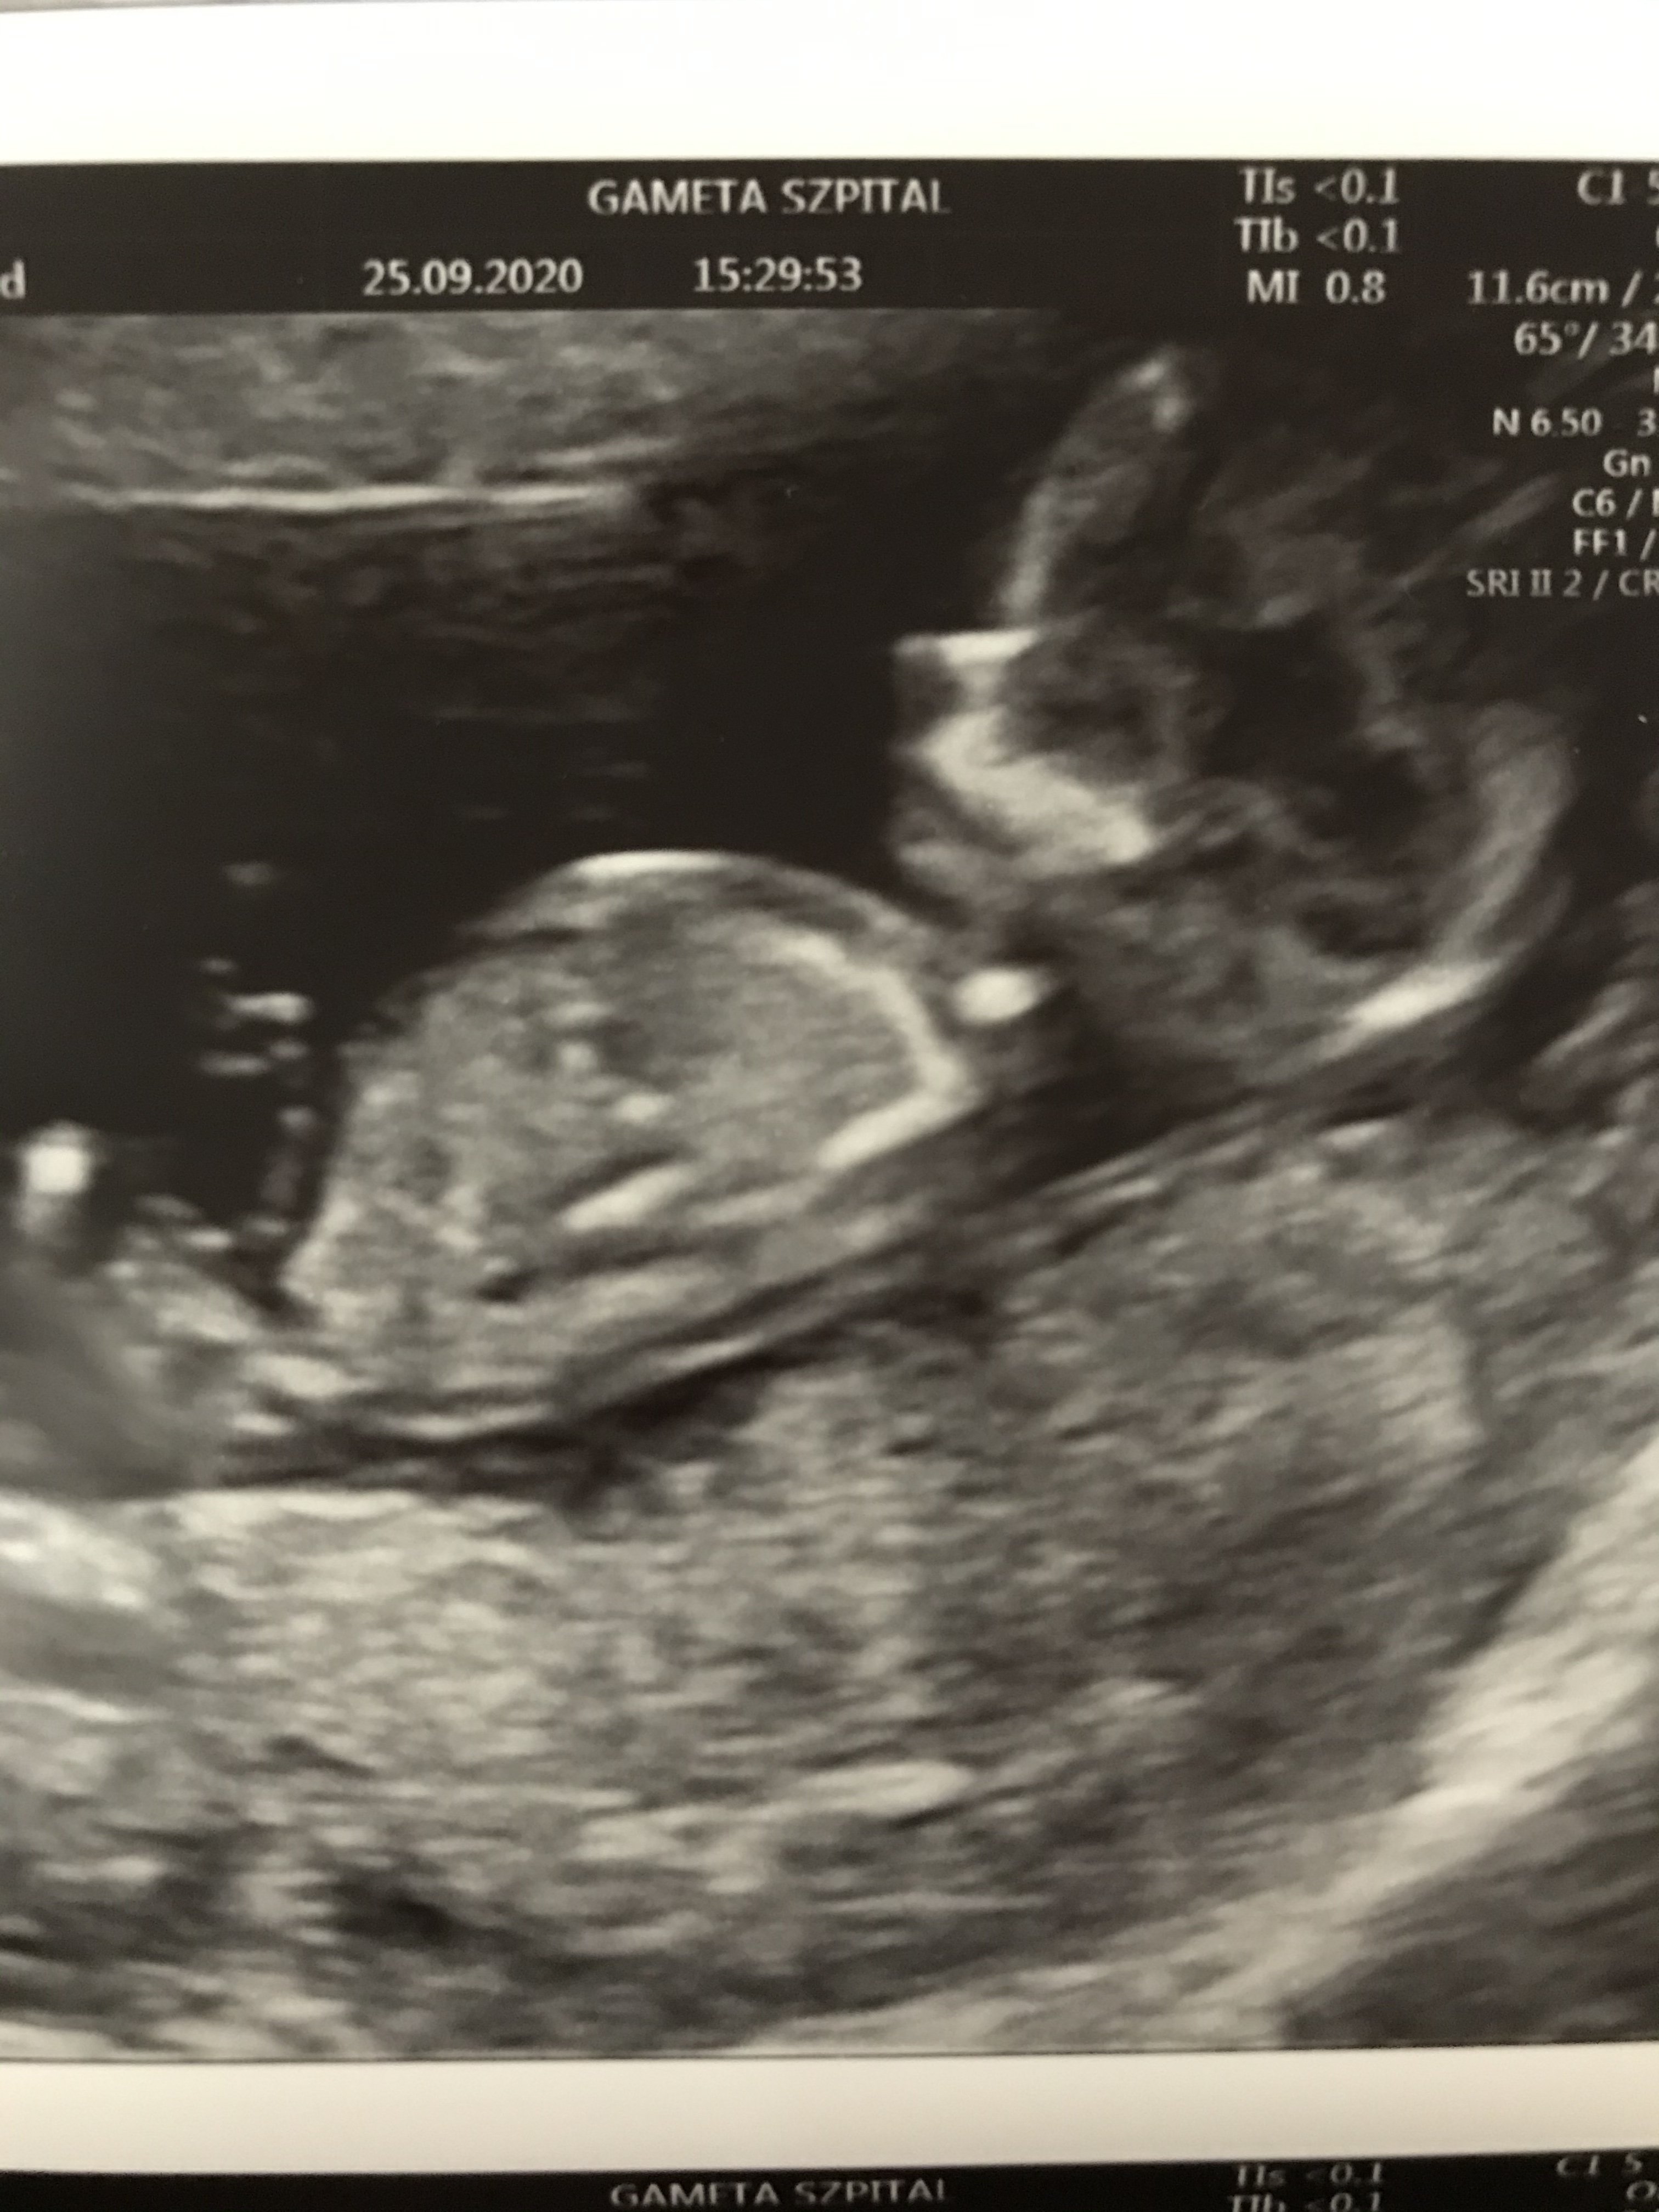

Dziewczyny 😄

Jestem po badaniu i na tą chwilę u Dzidziusia wszystko jest dobrze ❤ Poryczałam się oczywiście ze wzruszenia już u lekarza🙈 Prawdopobnie to córunia 😍 Rozpłynęłam się jak kostka lodu na słońcu ❤❤❤

• 02F2340D-F522-4FBA-9A54-6C5529B8BD18.jpeg

02F2340D-F522-4FBA-9A54-6C5529B8BD18.jpeg

954,8 KB · Wyświetleń: 126